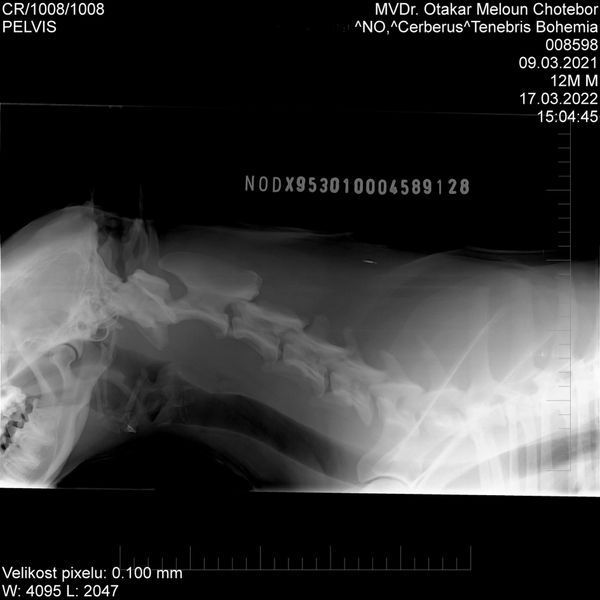

HD: A

Spondy: Free